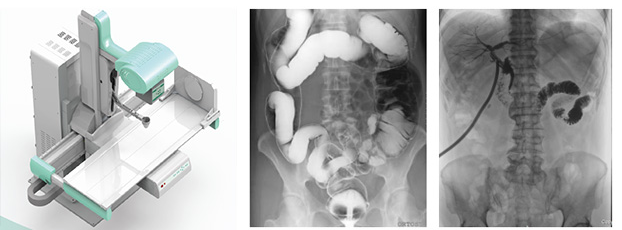

3、要擁有適宜床體高度的動(dòng)態(tài)檢查床及全面的床體運(yùn)動(dòng)功能,以輕松實(shí)現(xiàn)各種普通及特殊造影檢查,如食道造影、消化道造影、結(jié)腸雙對(duì)比造影、T管造影、靜脈腎盂造影(IVP)等。同時(shí)動(dòng)態(tài)dr要支持醫(yī)生回放造影視頻,并可以抽幀,輔助疾病診斷。